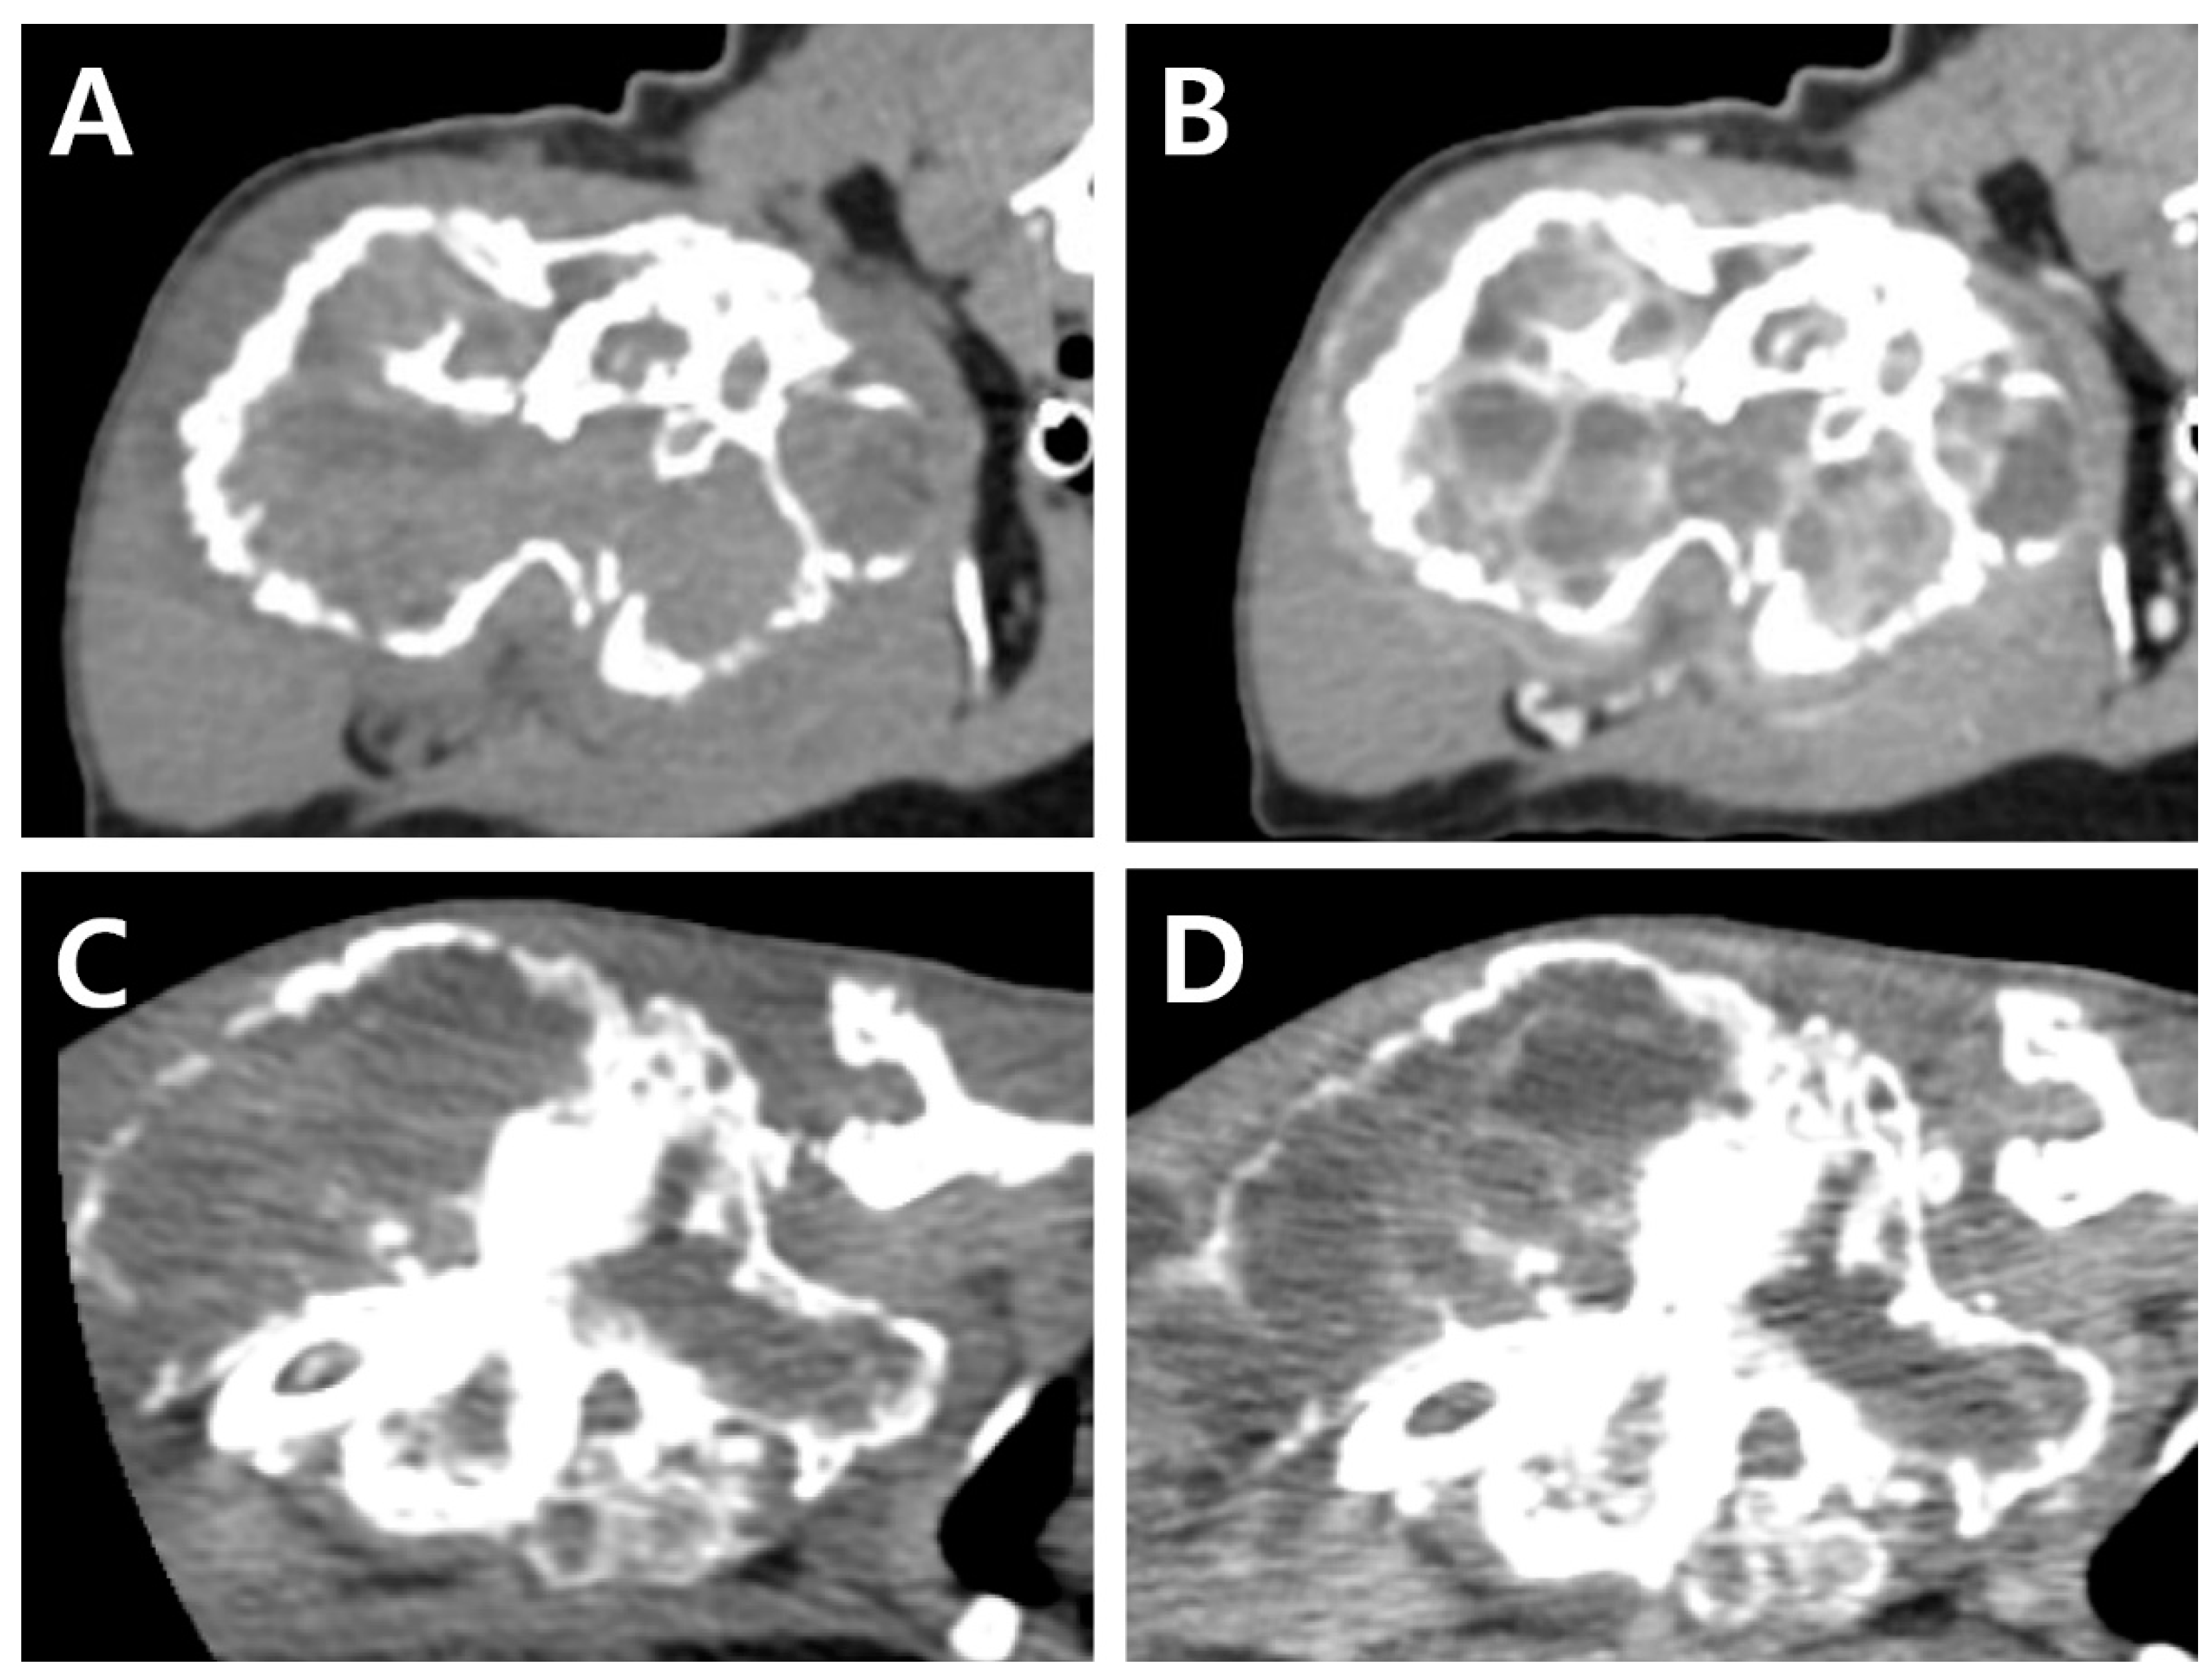

CT (Revolution®; GE Healthcare, Waukesha, WI, US) images were acquired before and after intravenous injection of the contrast medium (Omnipaque 300; GE Healthcare, Milwaukee, WI, USA). Consequently, a lytic expansile hypoattenuating bony mass (3.8 cm × 3.6 cm × 6.3 cm, Figure 2A) was identified between the humeral head and the mid-diaphysis. Severe cortical and medullary destruction, a sclerotic transition zone, and enriched vascularity were also noted around and inside the bony mass. Soft tissue blood density was observed in the lesion. Moreover, a periosteal reaction was observed around the acromion and glenoid cavity, with mild cortical destruction in the scapula. A post-contrast CT scan revealed contrast enhancement of the soft tissue adjacent to the mass. Homogeneous fluid attenuating signal intensity of cystic content and thin rim enhancement of margin and internal septa were also identified. (Figure 2B). The axillary lymph node was slightly enlarged (1.7 cm × 1.5 cm × 0.68 cm).

A complete blood count revealed severe anemia (hematocrit, 20.0%, reference range [RR] 30.3–52.3%). Four months after the initial presentation, a CT examination was performed again prior to the surgery (Figure 2C,D). Compared to the CT findings on initial examination, the mass had expanded dramatically in various planes. The overall thickness of the cortex of the mass had decreased, showing greater destruction of the medulla. Cortical destruction of the acromion and glenoid cavity was also identified, showing a more irregular surface due to the periosteal reaction. On three-dimensional volume-rendered images, osteolytic changes in the cranio-proximal region were more prominent, resulting in poor lesion margination at the time of the second presentation. In addition to the osteolytic changes, spiculated osteoid and areas of marked contrast enhancement were clearly visible, suggesting vascular proliferation in the surrounding soft tissue (Figure 3). The ipsilateral axillary lymph node had enlarged (1.9 cm × 1.75 cm × 0.79 cm) since the previous examination.

Figure 2. CT images at initial presentation (A,B). Pre-contrast image (A), post-contrast image showing contrast-enhancement of the surrounding tissues and vessels within the mass (B). CT Images at the second presentation (4 months after initial presentation) (C,D). Pre-contrast image (C), and post-contrast image (D). Note, regardless of the change in the size of the mass, fluid attenuating cystic lesion with rim enhancement of margin and internal septa are consistently identified.